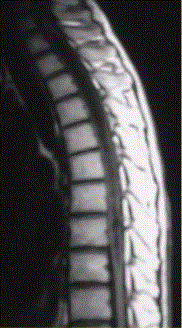

问题 患者女,45岁,胸部不适。影像学检查结果如下图所示。 对病变定位、定性诊断有价值的征象为

选项 A.脊椎增粗 B.邻近蛛网膜下腔变窄 C.病变边界清晰 D.病变特点为一个大囊,其内见一明显强化的结节影 E.病灶内有分隔 F.病灶内可见明显结节样强化

答案 ABCDF